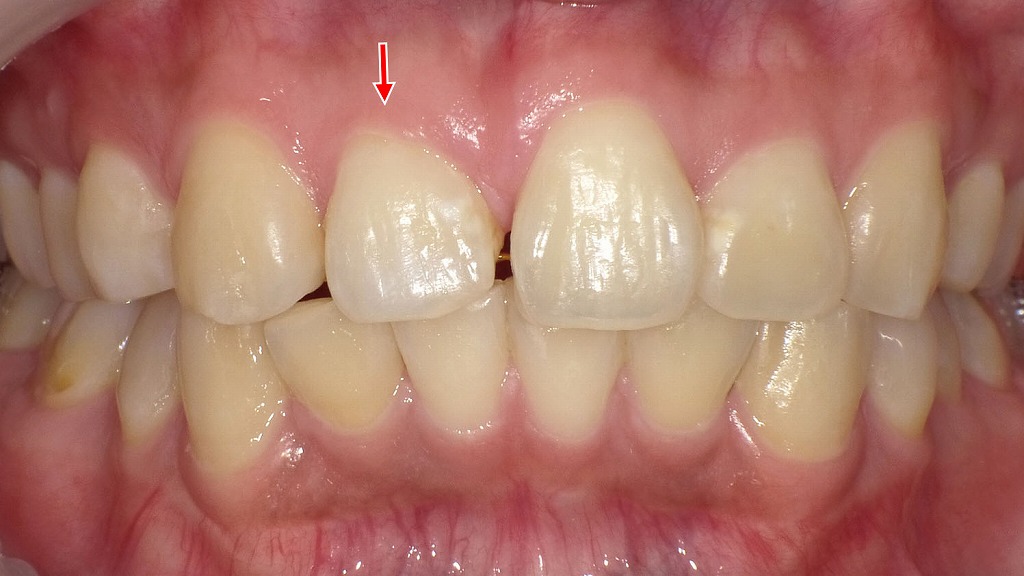

右上顎1番が短く小さいことで生じていた前歯のすき間に対し、ラミネートベニア治療を行った症例です。歯を大きく削らず、歯の表面に薄いセラミックを貼り付けることで、歯の長さ・幅・形態を自然に調整しています。周囲の歯とのバランスが整い、審美性と清掃性の両立が図られました。前歯のすき間や形の違和感に対する低侵襲な治療法の一つです。